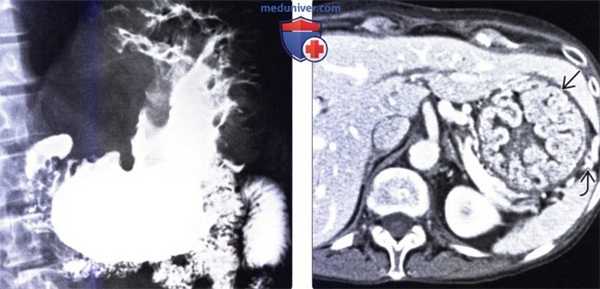

(Слева) На рентгенограмме, полученной при рентгеноскопии верхних отделов ЖКТ, определяется выраженное диффузное утолщение складок в области тела и дна желудка, относительно мало выраженное в антральном отделе. Обратите также внимание, что бариевая взвесь недостаточно хорошо покрывает слизистую оболочку.

(Справа) На КТ с контрастным усилением у женщины 68 лет с подтвержденной болезнью Менетрие определяется в значительной степени выраженное утолщение складок в области дна и тела желудка, идущих параллельно полнокровным сосудам желудка. Толстые, извитые складки напоминают извилины головного мозга.

2. Рентгенография при болезни Менетрие:

о В значительной степени утолщенные, дольчатые складки в области дна и тела желудка, относительно мало выраженные в антральном отделе

о Может определяться утолщение складок желудка даже в антральном отделе

о Локальный участок гипертрофии складок в области большой кривизны

о Гигантские опухолевидные извитые складки, напоминающие извилины головного мозга

о Желудок остается эластичным и растяжимым

о Избыточное количество муцина может разводить бариевую взвесь и снижать адгезию бариевой взвеси к слизистой

3. КТ при болезни Менетрие:

• Выраженное утолщение слизистой и подслизистого слоя

• Полнокровие артерий и вен желудка

• Нет изменений со стороны окружающих желудок тканей